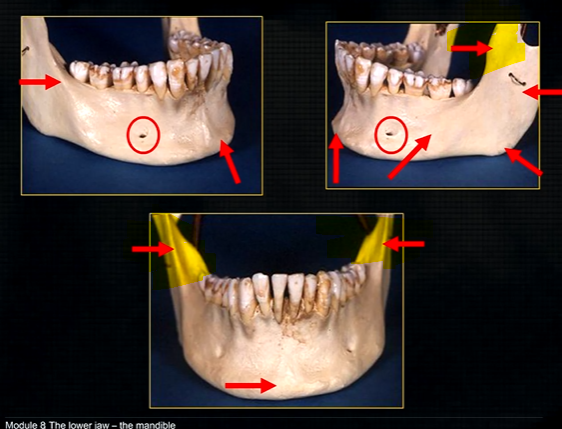

mandible - the lower jaw

mental prominence

body

mental foramina

dense bony prominence of the external oblique ridge

angle

coronoid process - and ascending rami on both sides????

anterior lingual/inner aspect of the mandible

genial tubercules - muscles of the tongue and neck attach here

mylohyoid ridge - mylohyoid attaches to form the floor of mouth

mandible varies in cross sectional thickness

mental foramen - black radiolucency - near 1st and 2nd premolars

sockets of the teeth are represented by thin, white, opaque lines → ‘ lamina dura’

dense, white, radiopaque line → dense bone of mylohyoid ridge

underneath mylohyoid ridge - looks more radiolucent → this is due to the lingual indentation of submandibular fossa

dense cortical bone of the lower border

radiolucent shadow created by the lingual pit

lower occlusal

small bony spurs of the genial tubercles